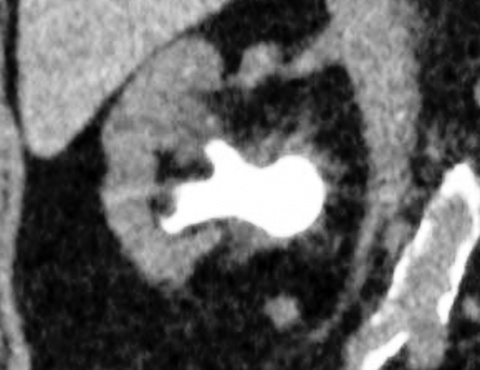

Ergibt sich in der Zusammenschau der Diagnostik der Verdacht auf eine Harnsteinerkrankung, sollte eine Niedrig-Dosis-CT des Abdomens zur genauen Lokalisation des Konkrements und zur weiteren Therapieplanung erfolgen. Hierbei kann die Bestimmung der Hounsfield-Einheiten[1] Hinweise auf die Steinzusammensetzung geben.